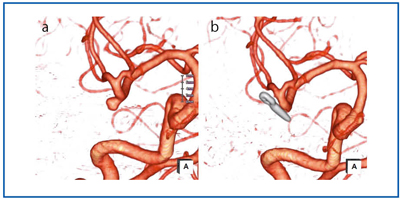

■脳動脈瘤

CTAは、治療方針決定など術前の情報としてはもちろんのこと、術後の確認や説明用としても重要な位置付けとなっている。主に、脳全体の血管情報を得る目的として検査を行うが(図3)、特に、術前の動脈瘤の形状や穿通枝との位置関係の確認、術後のclip確認などに重点を置いて検査を行っている(図4)。

図4 脳動脈瘤クリッピング

a:術前、b:術後